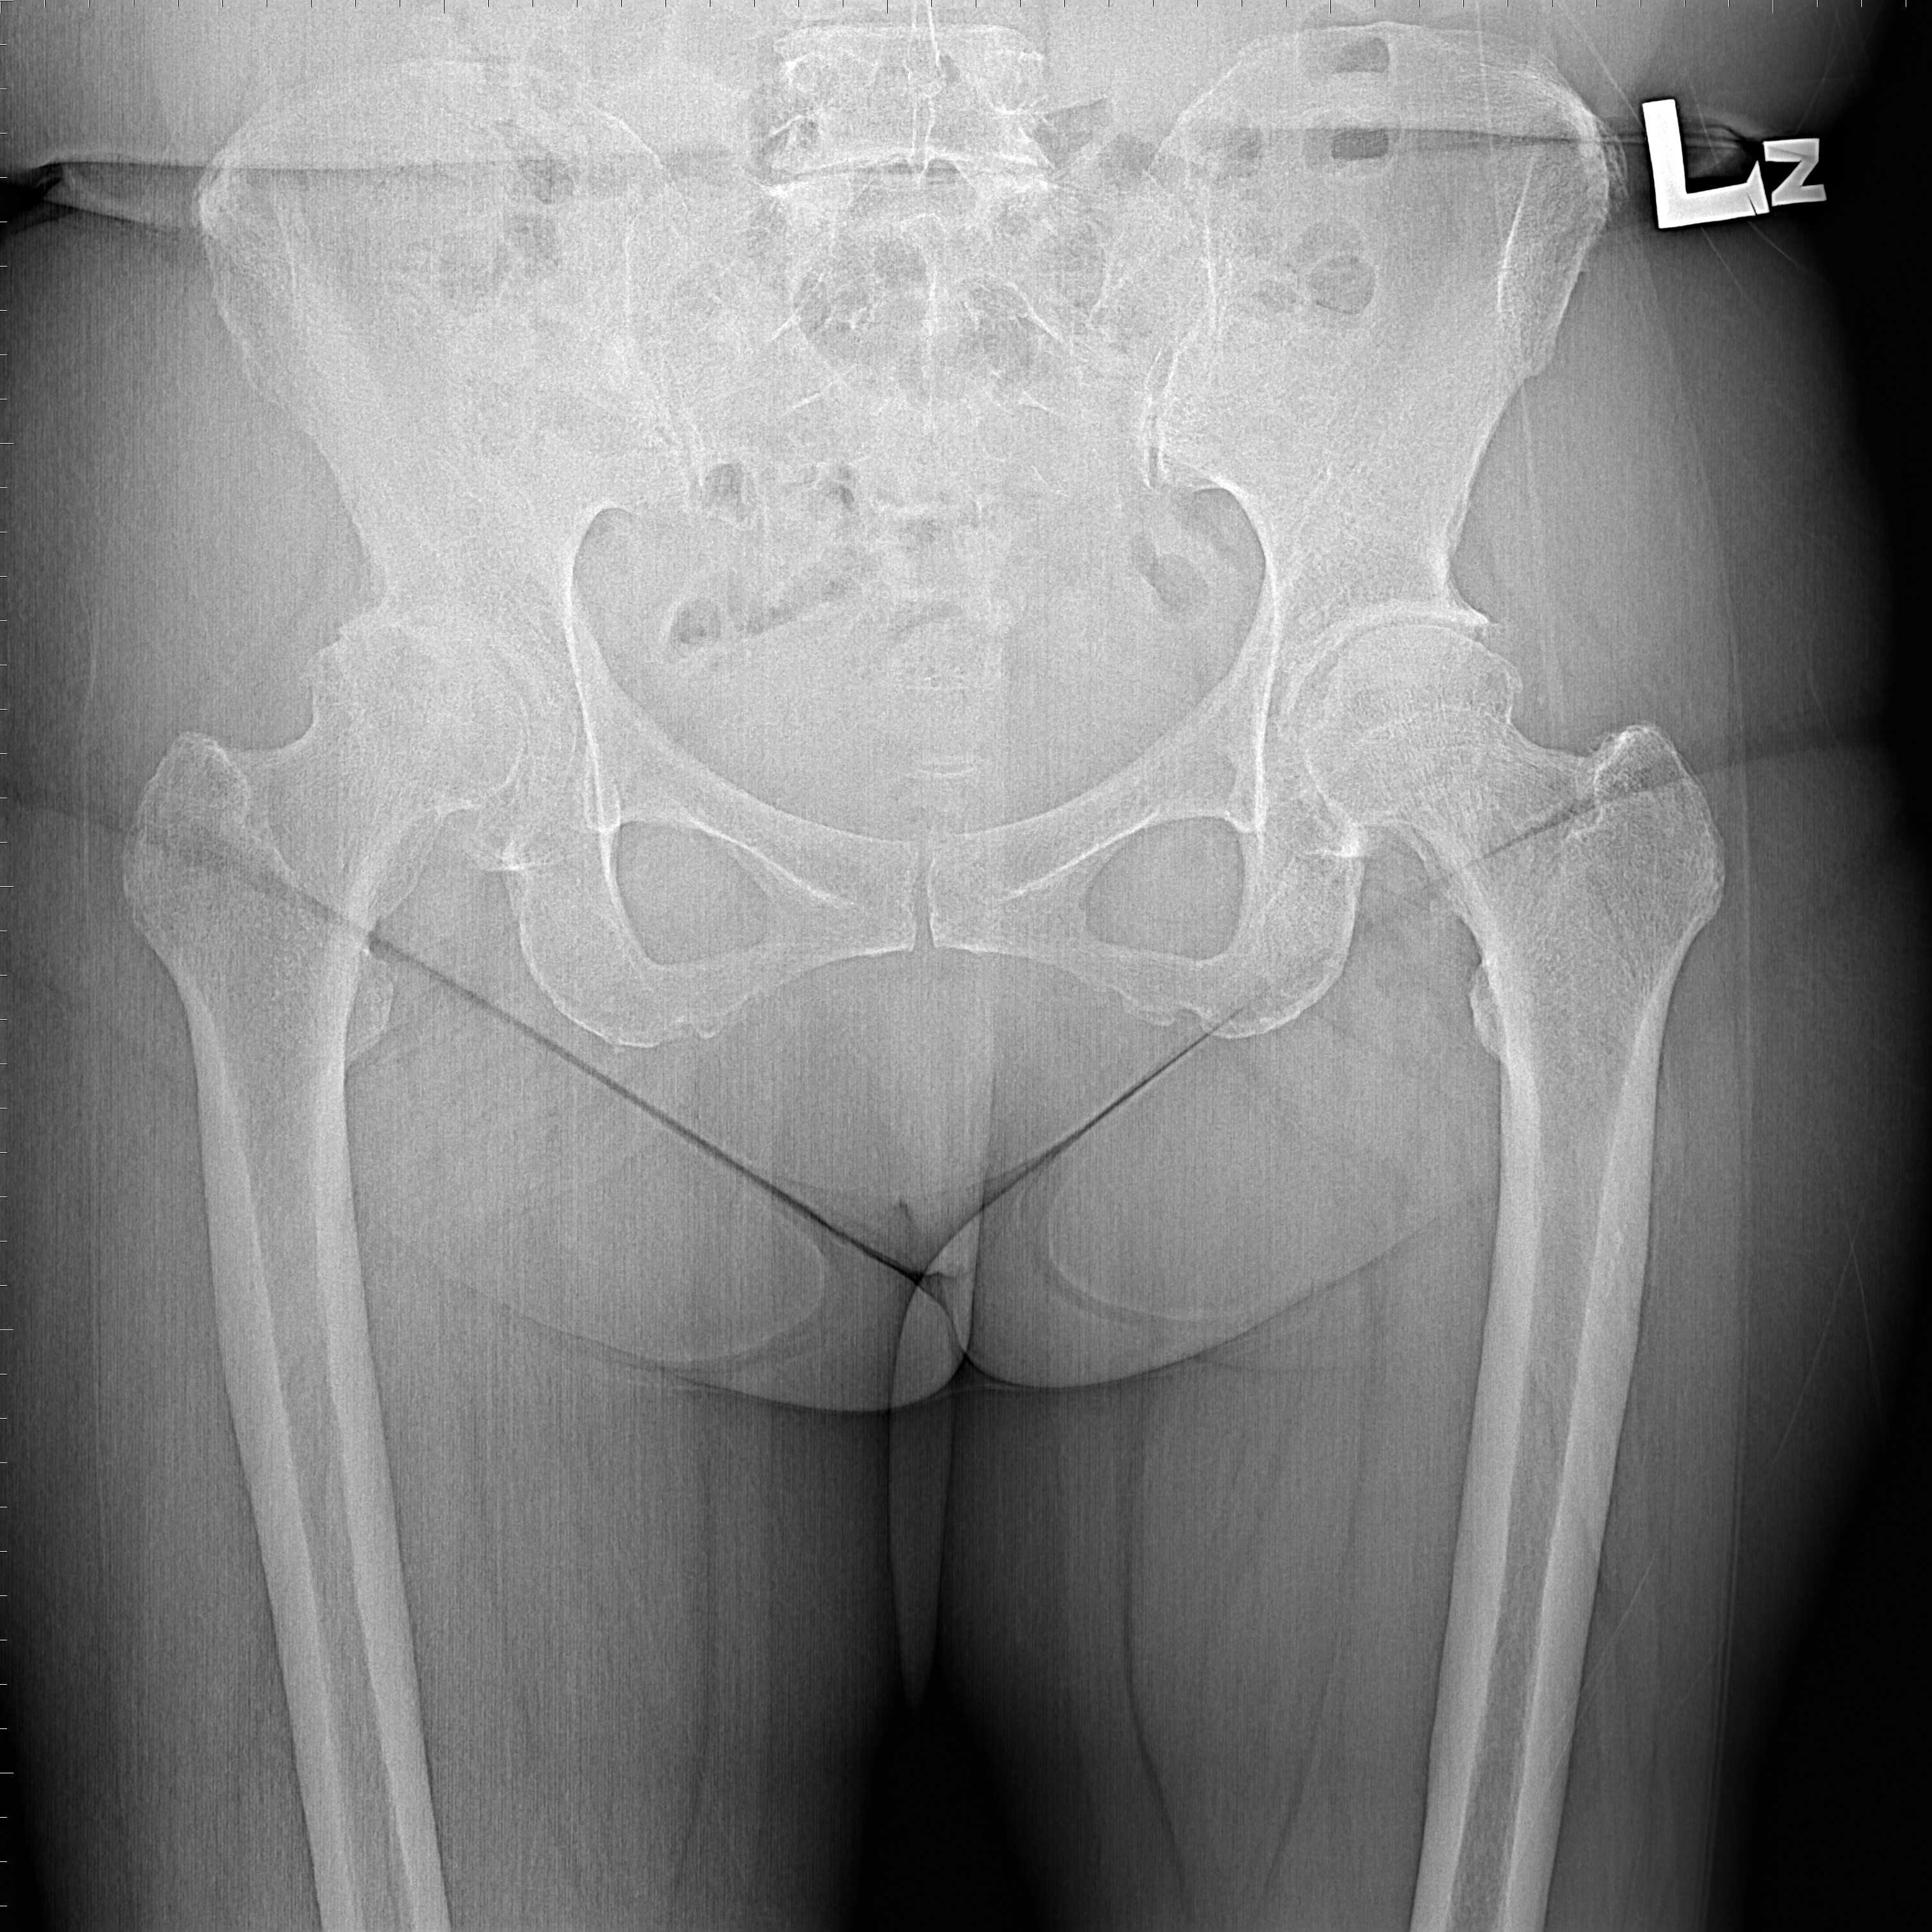

機器手臂手術 首頁 案例分享 髖關節手術 機器手臂手術 72歲 楊女士 退化性關節炎 術前 術後 60歲 彭先生骨股頭壞死 術前 術後 53歲 王女士退化性關節炎(DDH先天發育不全 CROWE TYPE 2) 術前 術後 83歲林女士退化性關節炎 術前 術後 83歲林女士退化性關節炎 術前 術後 楊女士 70歲 術前 術後 蔡女士 60歲 術前 術後